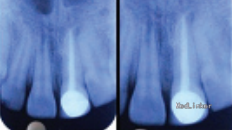

检查见21牙周围牙龈正常,无瘘道,叩(+)。 X线片发现21牙根中部有一髓石,牙冠颈部也有一髓石。

考虑到患者21牙根管内有两处髓石,而且在进行21牙根管治疗过程中疼痛加剧,怀疑在根管治疗过程中,髓石被加压推至根中,从而导致无法完全清除牙髓组织,引起自发疼痛。 利用10号K挫和EDTA从髓石周围疏通,辅助超声荡洗将髓石取出,约3mm大小。

髓石多发生于成年人根管,较少见于儿童。临床中要认真分析根管影像,勿要像此病例中因医源性推挤髓石导致髓石堵住根管,加重病人疼痛,造成根管治疗失败。较大的髓石可以通过裂钻将其破裂取出,但是此种方法对牙体组织损伤较大,且较易发生穿孔。此时可以利用EDTA和小号扩锉针疏通,配合超声仪器取出。 DOI: 10.7860/JCDR/2015/13010.6047